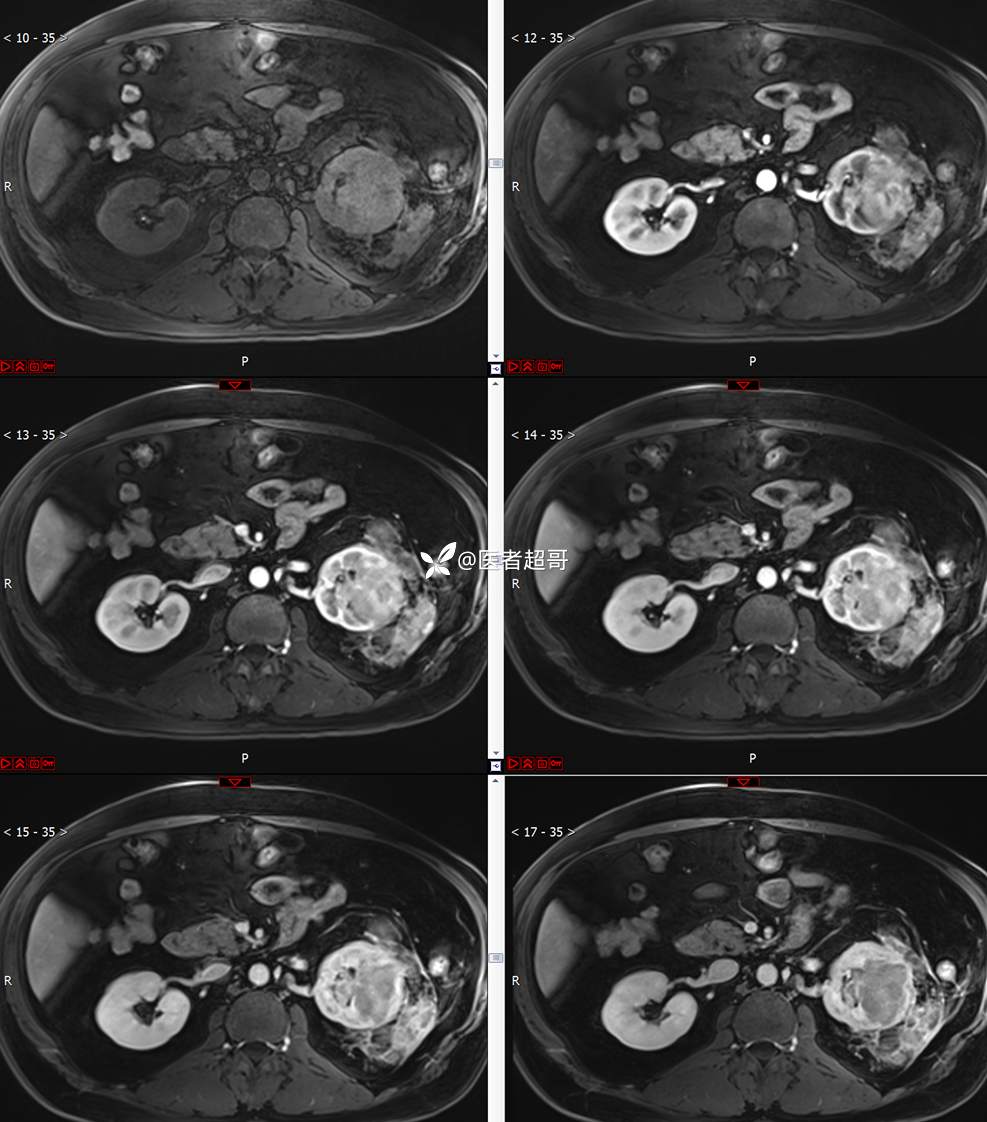

主 诉:查体发现左肾肿物9天。

现病史:患者9天前于附属医院行常规腹部CT检查时,发现左肾占位性病变并肾周脂间隙软组织增多,自述无明显腰腹部不适,无尿频、尿急、尿痛及肉眼血尿,未予特殊治疗,患者近期无头晕头迷,胸闷气急,腹胀腹泻及其他部位明显不适,遂至我院就诊,门诊以“肾肿物”收入院,患者自发病以来,精神可,睡眠饮食可,大便正常,体重无明显减轻。